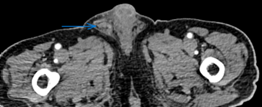

Evident dilation of the left ureter -- yellow outline. Green outline -- Chordoma (Courtesy Dr. V. Penopoulos)